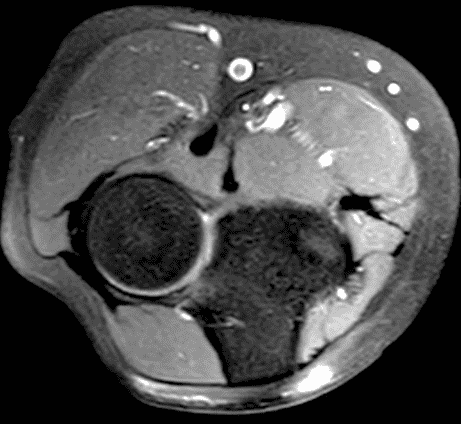

A 55-year-old man complains of pain, numbness, and tingling in the ulnar aspect of the hand and in the small and ring fingers. The symptoms are more severe with elbow flexion and during sleep. He has no muscle weakness or history of trauma. Axial T1-weighted (1A, 1B) and fat-suppressed, fluid-sensitive (1C, 1D) images are shown. What are the findings? What is your diagnosis?

Figure 2: At the level of the cubital tunnel (2A and 2C), identifiable by the thin cubital tunnel retinaculum (yellow arrow), the ulnar nerve (red arrow) is focally enlarged and hyperintense compared to the nerve more distally (2B and 2D), where it lies between the two heads of the flexor carpi ulnaris muscle (asterisks). No soft tissue mass is present.